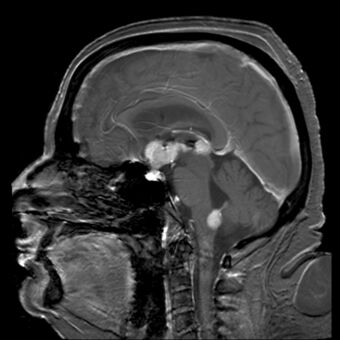

Brain magnetic resonance imaging showing primary central nervous system B-cell non-Hodgkin lymphoma of the sella turcica and hypothalamus, continuing to the tectum (intensely white areas in the middle).